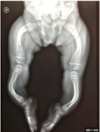

This cast of the bronchial tree is formed of inspissated mucus and was coughed up by a patient with what pathology? [1]

A

Asthma:

The outpouring of mucus from hypertrophied bronchial submucosal glands, the bronchoconstriction, and dehydration all contribute to the formation of mucus plugs that can block airways in asthmatic patients.